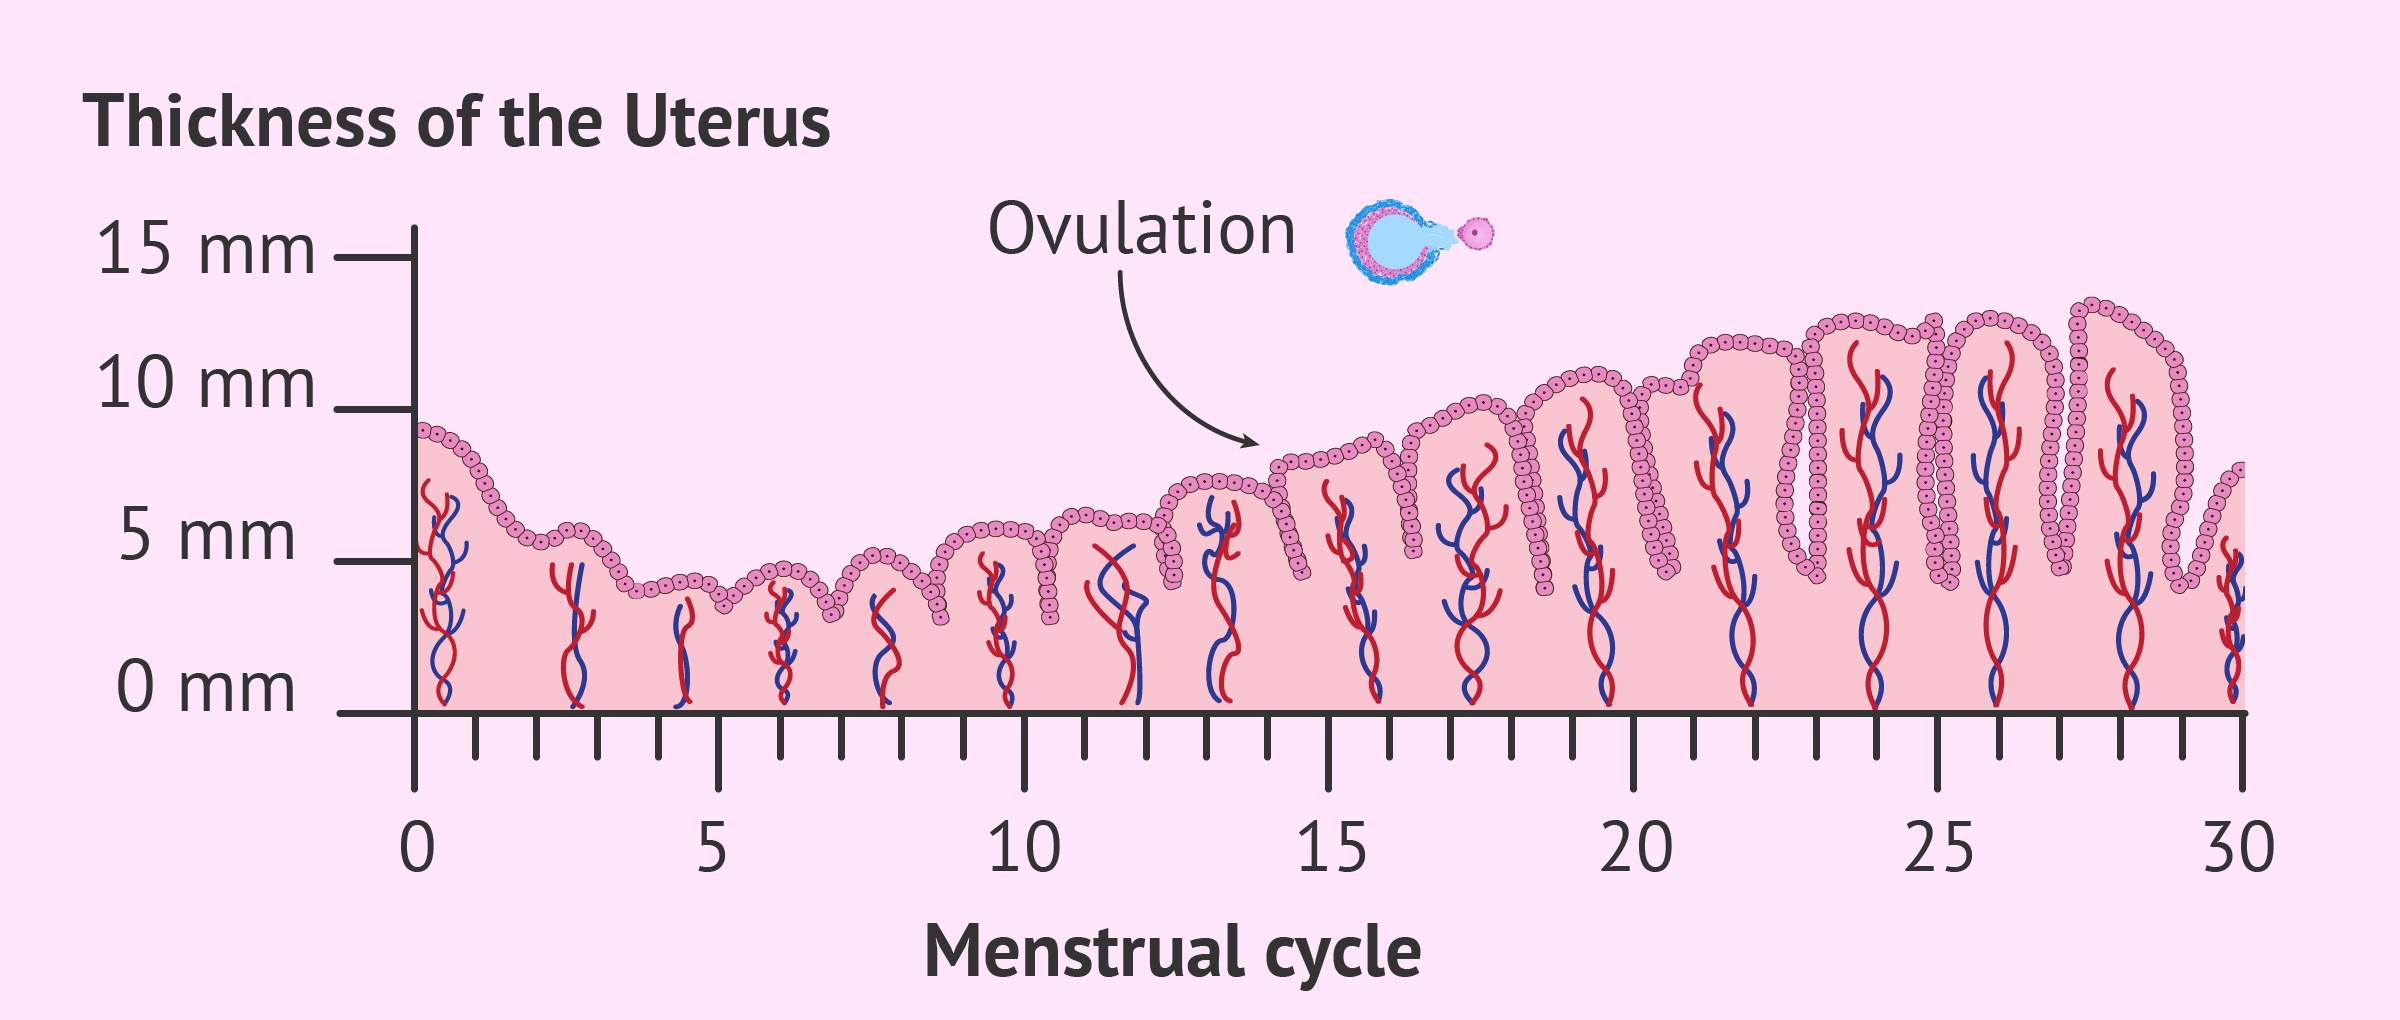

Uterine Lining Thickness Chart .

Menstrual Cycle Graphing .

Uterus And The Menstrual Cycle The Uterine Cycle .

The Menstrual Cycle Assignment A Sixteen Year Old Girls .